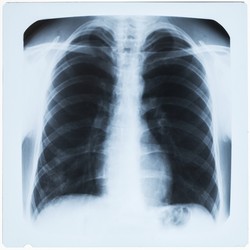

Szybka diagnoza zapalenia płuc

Prawidłowa identyfikacja patogenów wywołujących zapalenie płuc jest kluczowa dla zapewnienia skutecznego leczenia. Innowacyjna platforma oparta na cząsteczkach ma zapewnić prawidłową diagnozę w bardzo krótkim czasie.

Zakażenia dróg oddechowych wywoływane przez patogeny bakteryjne, wirusowe, grzybiczne i inne są odpowiedzialne za miliony zgonów każdego roku. Zakażenia dróg oddechowych nabywane w społeczności są nazywane pozaszpitalnym zapaleniem płuc (CAP), a te nabyte w szpitalu są nazywane szpitalnym zapaleniem płuc (HAP) i obejmują zapalenie płuc związane z mechaniczną wentylacją płuc (VAP). Obecnie, diagnostyka laboratoryjna zakażeń dróg oddechowych zajmuje przynajmniej dwa dni, w czasie których pacjenci otrzymują antybiotykoterapię empiryczną. Oprócz tego, że jest nieskuteczna, taka terapia może również pogarszać rokowanie. Zakres finansowanego przez UE projektu RID-RTI (Rapid identification of respiratory tract infections) obejmował opracowanie platformy diagnostycznej do szybkiego diagnozowania różnych rodzajów zapalenia płuc w czasie poniżej dwóch godzin. Opracowana platforma opierała się na molekularnym wykrywaniu patogenów i obejmowała izolację DNA patogenu z próbek z dróg oddechowych. W pierwszym etapie, naukowcy zidentyfikowali kilka celowych patogenów, a także geny oporności antybiotykowej do amplifikacji PCR. Dla każdego rodzaju zapalenia płuc (CAP, HAP i VAP) wybrano kilka patogenów specyficznych dla zakażeń dróg oddechowych. W każdym przypadku zaprojektowano i udoskonalono multipleksowe badania PCR w czasie rzeczywistym, wraz z sondami do hybrydyzacji. Powstała platforma obejmowała przygotowanie próbki w pojedynczej kasecie, amplifikację kwasów nukleinowych i detekcję poprzez hybrydyzację. Ponadto urządzenie RID-RTI zawierało kontrolę przyrządu, analizę i oprogramowanie interfejsu użytkownika, a kaseta HAP/VAP przeszła badania analityczne. Zważywszy że zakażenia dróg oddechowych są nadal trudne do zdiagnozowania z uwagi na udział wielu patogenów, platforma RID-RTI stanowi doskonałe narzędzie zapewniające prawidłową diagnozę. Co najważniejsze, oszczędność czasu gwarantowana przez tę metodę ułatwi podejmowanie szybkich decyzji dotyczących wdrożenia antybiotykoterapii i poprawi rokowania pacjenta.